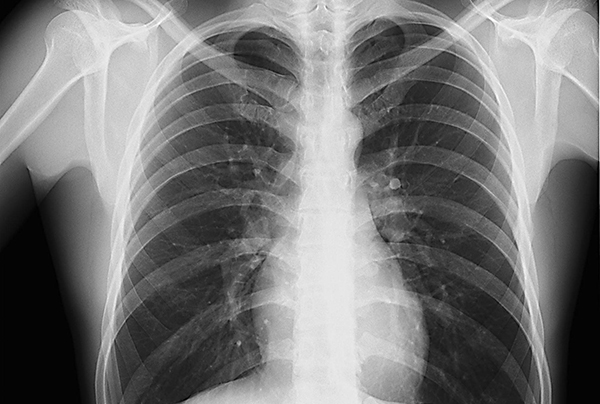

Radiografía

La radiografía del corazón nos permite comprobar si el tamaño del corazón es el correcto, para saber si este músculo se ha engrosado demasiado, o si tiene un tamaño más pequeño del que correspondería por un incorrecto desarrollo. Es una prueba meramente informativa, pero que se suele hacer para descartar cualquier problema cardíaco.